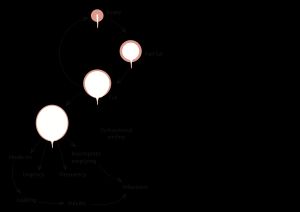

배뇨는 신경, 근육, 척수, 뇌가 관여하는 복잡한 활동이다. 방광은 복부 아랫부분에 위치한 풍선 모양의 근육으로, 소변을 저장했다가 요도를 통해 배출한다. 방광은 방광 배뇨근과 괄약근이라는 두 가지 근육으로 구성된다. 방광 배뇨근은 소변을 저장하고 배출하기 위해 수축하는 근육 주머니이며, 괄약근은 방광 바닥이나 옆면에 연결되어 자동으로 수축하여 소변을 유지하는 원형 근육 그룹이다. 방광 아래의 골반 기저 근육은 수축하여 소변을 막을 수 있다.

소변은 신장에서 제거된 물과 노폐물로, 풍선 모양의 기관인 방광에 저장된다. 방광은 소변이 몸 밖으로 배출되는 관인 요도와 연결된다.[21]요실금과 배뇨는 요도 폐쇄와 방광 배뇨근 활동 (방광 근육) 사이의 균형을 포함한다. 배뇨하는 동안 방광 벽의 방광 배뇨근이 수축하여 소변을 방광 밖으로 밀어내어 요도로 보낸다. 동시에, 요도를 둘러싼 괄약근이 이완되어 소변이 몸 밖으로 배출된다. 요도 괄약근은 방광 출구를 닫아 소변이 몸 밖으로 배출되는 것을 막는 근육 링이다. 요도 압력은 정상적으로 방광 압력보다 높아서 소변이 방광에 남아있고 요실금을 유지한다.[22] 요도는 골반 기저근과 조직에 의해 지지되어 단단히 닫힐 수 있다. 방광 배뇨근, 요도 괄약근, 지지 조직 및 신경 사이의 이러한 균형에 손상이 발생하면 일부 유형의 요실금으로 이어질 수 있다.

예를 들어, 복압성 요실금은 보통 요도 괄약근의 부적절한 폐쇄의 결과이다. 이것은 괄약근 자체, 괄약근을 지지하는 근육 또는 괄약근에 공급하는 신경의 손상으로 인해 발생할 수 있다. 남성의 경우, 이 손상은 보통 전립선 수술이나 방사선 치료 후에 발생하며,[17] 여성의 경우, 출산과 임신으로 인해 발생한다.[23] 복부 내부의 압력 (기침 및 재채기)은 일반적으로 요도와 방광 모두에 동일하게 전달되어 압력 차이가 변하지 않고 요실금이 유지된다. 괄약근이 부적절하면 이러한 압력 증가는 소변을 괄약근에 밀어 넣어 요실금으로 이어진다.

또 다른 예는 절박성 요실금이다. 이 요실금은 방광 배뇨근 (방광 근육)의 갑작스럽고 강력한 수축과 관련되어 배뇨에 대한 강렬한 느낌을 유발하고, 사람이 제 시간에 화장실에 가지 못하면 요실금으로 이어진다. 이 증후군은 과민성 방광으로 알려져 있으며 방광 배뇨근의 기능 장애와 관련이 있다.[24]